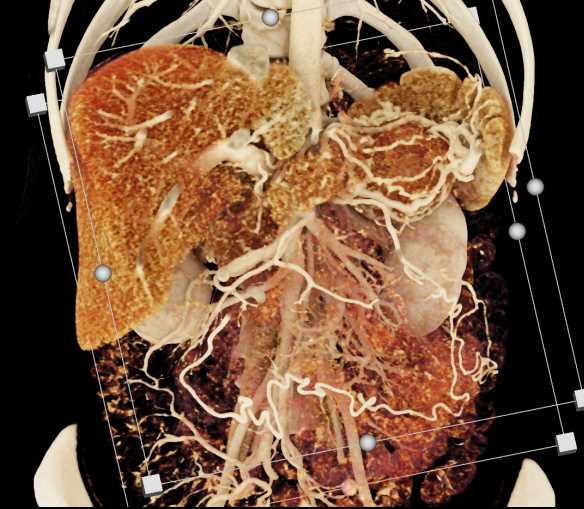

Neuroendocrine Tumor Pancreas